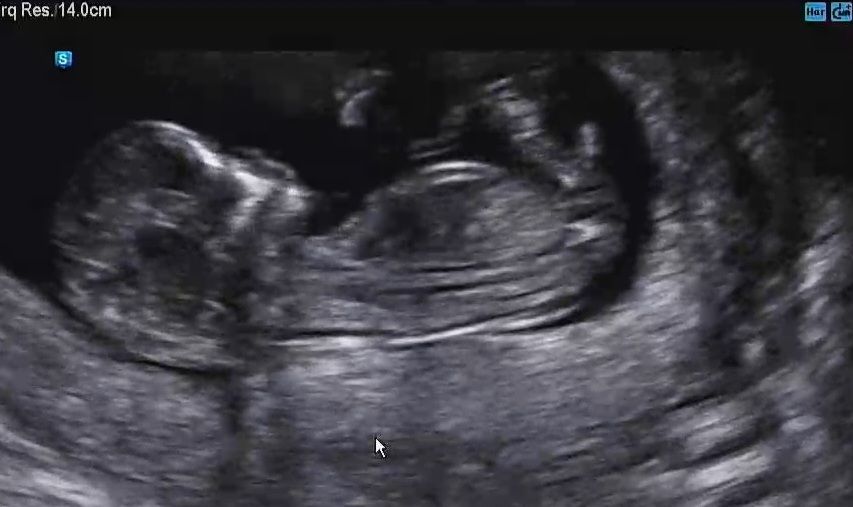

12주 촘파 보고왔는데 둘찌는 아들일까요 딸일까요 ㅎ 저는 각도법 우찌 보는지 모르겠네요 ㅠㅎㅎ